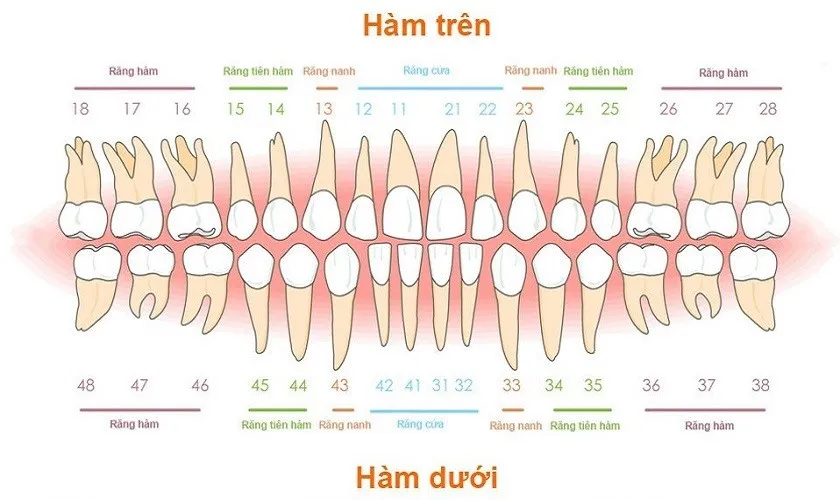

Các loại hàm răng là kiến thức cơ bản nhưng vô cùng quan trọng trong việc hiểu và chăm sóc sức khỏe răng miệng. Dù bạn đang

Câu hỏi “con nguoi co bao nhieu rang” luôn là thắc mắc phổ biến của nhiều người khi muốn hiểu rõ hơn về sức khỏe răng miệng.